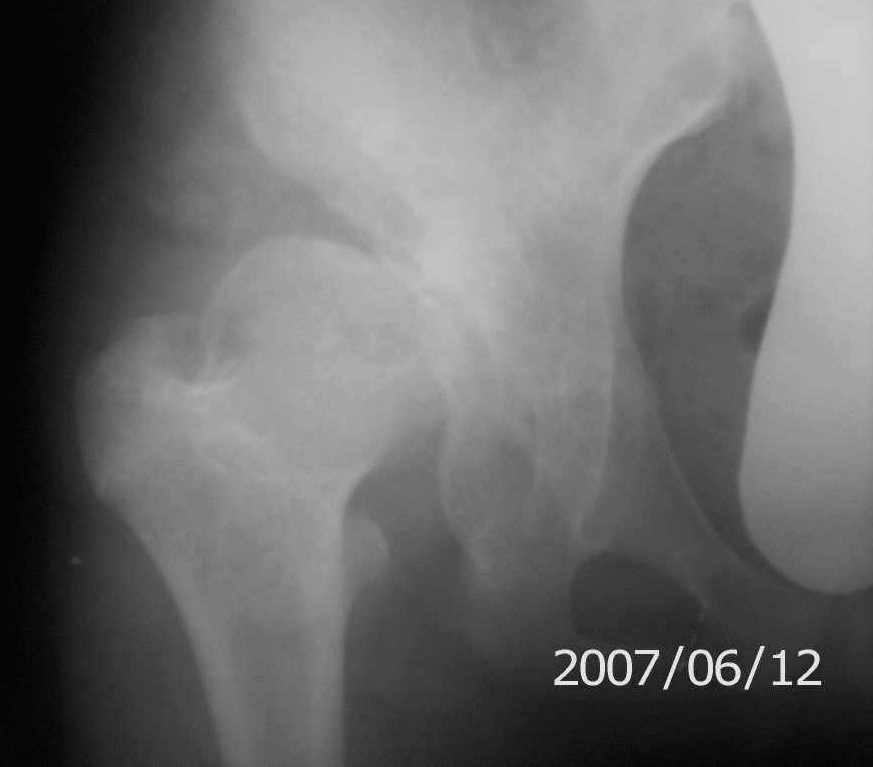

снимки

On x-rays coxa magna, shallow true + pseudoacetabulum.Options: salvage

( Shelf /Chiari) or triple osteotomy.Trudno otvetit bez at least basic x-rays.

Ацетабулюм крайне недоразвит. Есть высокий подвывих, можно даже сказать вывих с формированием ложного ацетабулюм. Для головки нет покрытия совсем и расположена она высоко.

На мой взгляд - SHORTENING OSTEOTOMY , VARUS если надо (на основании снимка во внутренней ротации), репозиция головки, CHIARI OSTEOTOMY или SHELF OPERATON Спасибо за интересный случай.